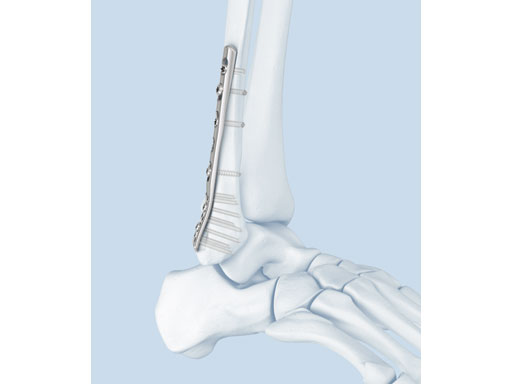

The LCP posterolateral distal fibula plate offers six round locking holes and two coaxial holes distally which accept 2.4 and 2.7 mm locking and cortex screws to provide multiple screw options. The distal holes are slightly divergent to help prevent screw pullout. The coaxial hole accepts both locking and cortex screws and its recess for screw heads minimizes screw-head prominence by allowing the screws to sit more flush with the plate, creating a low-profile construct. Its posterolateral position allows it to be placed deep to the peroneal muscles, minimizing the risk of wound healing problems due to prominence. A 2.7 mm lag screw may be placed through the distal screw cluster, and a syndesmotic screw may also be placed through the plate.

The anatomically precontoured plate shaft is only 2.25 mm thick yet substantially stronger than the one-third tubular plate. The combination holes in the shaft accept 3.5 mm locking screws, 3.5 mm cortex screws, and 4.0 mm cancellous bone screws.